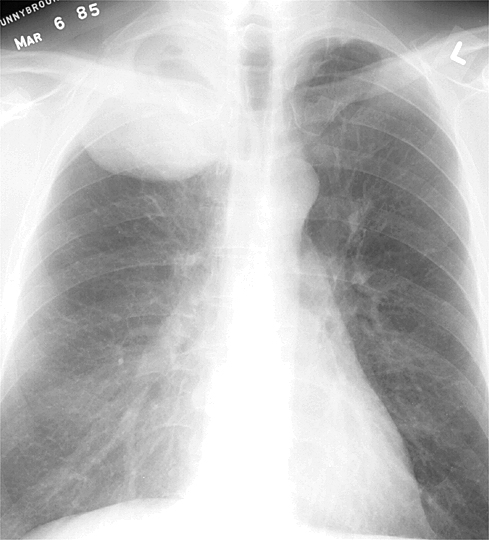

Диагностика и изображение опухолей легких